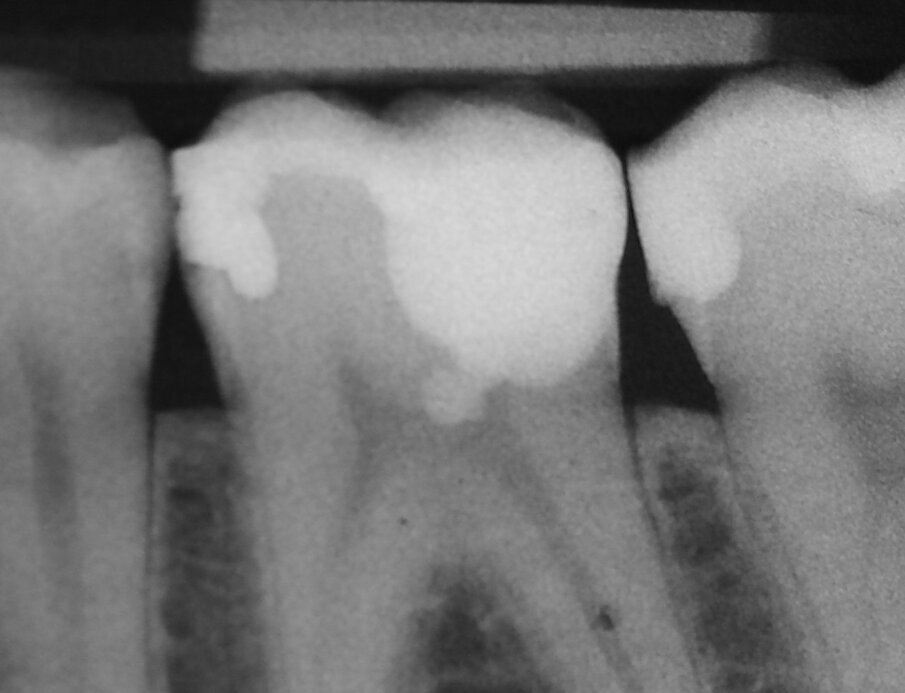

Per evitare l’estrusione di materiale da otturazione del canale radicolare in denti immaturi con apici aperti, si utilizza MTA come sigillo apicale. I risultati di molti studi hanno dimostrato che l’MTA induce più spesso la formazione di tessuto duro apicale e che il suo uso è associato ad una minore infiammazione rispetto ad altri materiali di prova (Simon et al. 2007) (Figg. 2a-2g).

Apecificazione